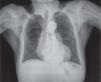

Se realizó una ecografía torácica que demostró una colección residual en forma de imagen fusiforme hipoecoica de 3,7 cm × 7 mm, por debajo de planos musculares hacia el esternón, junto a imagen lineal refringente situada en una estructura tubular anecoica por un resto de catéter o cable residual de marcapasos retirado. Se demostraron dichos cables residuales en una radiografía de tórax, donde se podían visualizar los dos cables abandonados, el más largo coincidente con la zona de la lesión granulomatosa conectado con el ventrículo derecho (fig. 3).

La radiografía de tórax anteroposterior muestra los electrodos residuales del marcapasos retirado, con las sondas en localización subclavicular, siendo la más larga la coincidente con el lugar de la lesión. El extremo contrario se sitúa en el ventrículo derecho. En la parte inferior de la radiografía puede observarse el electrodo de origen abdominal con su extremo libre en el ventrículo.